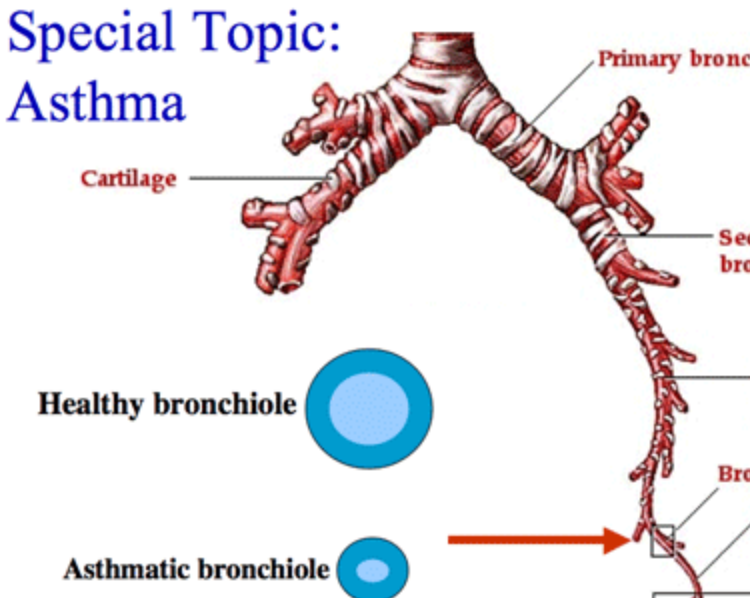

Cricoid cartilage

Bronchiole

Terminal bronchiole

Respiratory bronchiole